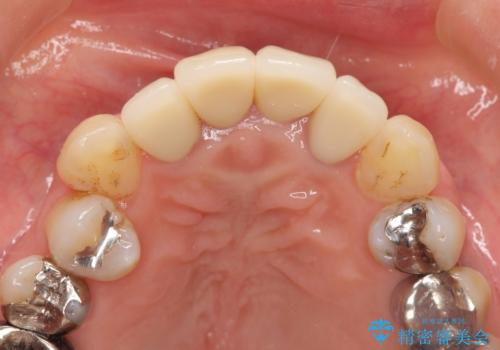

劣化したクラウンを除去し、再発した虫歯を徹底的に除去したのち根管治療・ファイバーコア築盛を行いジルコニアクラウン製作へと移ります。

- 52万円(仮歯・ファイバーコア・ジルコニアクラウン×4)費用は治療当時の料金となります

歯ぐきの位置は経年的に変化することがあります。その際にもジルコニアクラウンはクラウンの際が黒くなく目立ちにくく審美的なクラウンと言えます。